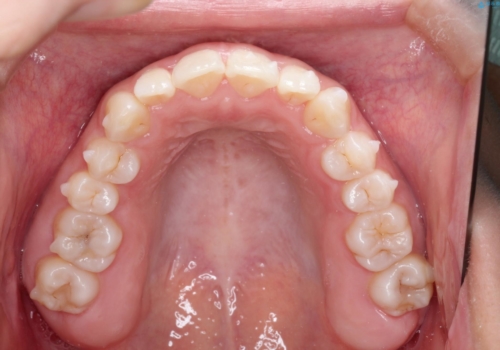

- 初診時には前歯部に捻転や叢生、臼歯部にも一部叢生が見られる状態でした。

インビザラインでの治療を計画し、行っていきました。

インビザライン治療により、捻転を含む歯列もしっかりと改善しています。

基本的な不正咬合部分は初回の30枚のマウスピースでほぼ改善しており、リファインメントでは前歯部の細かな調整など、患者様の要望を取り入れる形でシミュレーションをセットアップし、満足の行く結果に仕上がりました。